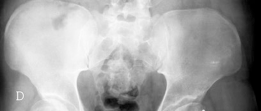

Radiographic evaluation must demonstrate a clear structural conflict, such as an extruded lateral head segment causing hinge abduction, but without advanced joint space narrowing. The presence of a "hinge" can often be confirmed dynamically under fluoroscopy or via abduction-internal rotation plain radiographs.

Standard radiographic series should include an anteroposterior pelvis, cross-table lateral, and false profile views of the affected hip. Functional views, such as maximum abduction and adduction radiographs, help quantify the degree of hinge abduction and the potential for concentric reduction.